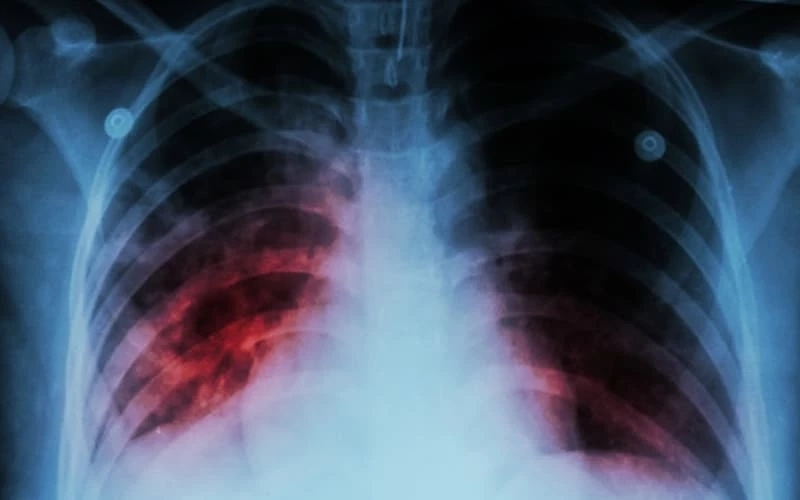

สำหรับประเด็นนี้ ทางด้าน นายแพทย์ธงชัย กีรติหัตถยากร อธิบดีกรมการแพทย์ เปิดเผยว่า วัณโรค เป็นโรคติดต่อในระบบทางเดินหายใจ เกิดจากเชื้อแบคทีเรียที่มีชื่อว่า Mycobacterium tuberculosis สามารถเกิดได้ในทุกอวัยวะของร่างกาย ได้แก่ เยื่อหุ้มปอด ต่อมน้ำเหลือง กระดูกสันหลัง ข้อต่อ ช่องท้อง ระบบทางเดินปัสสาวะ ระบบสืบพันธุ์ ระบบประสาท เป็นต้น

อย่างไรก็ดี ส่วนใหญ่มักเกิดที่ปอด ซึ่งแหล่งแพร่เชื้อที่สำคัญคือ เมื่อผู้ป่วยเป็นวัณโรคปอด ไอ จาม ถ่มน้ำลาย และขากเสมหะ ละอองเสมหะขนาดเล็กที่ถูกขับออกมาจะกระจายสู่อากาศและลอยค้างอยู่หลายชั่วโมง และเมื่อผู้อื่นหายใจรับเชื้อเข้าไปก็จะเกิดการติดเชื้อได้

วัณโรค (Tuberculosis หรือ TB) เป็นโรคติดต่อที่เกิดจากเชื้อแบคทีเรีย “ไมโคแบคทีเรียม ทูเบอร์คูโลซิส” ซึ่งสามารถติดต่อกันผ่านทางอากาศได้ด้วยการหายใจ การจาม การไอ หรือการอยู่ร่วมกับผู้ป่วยติดต่อกันเป็นเวลานาน ๆ ซึ่งวัณโรคสามารถเกิดได้ในอวัยวะทุกส่วนของร่างกาย แต่ส่วนใหญ่ 80% พบที่ปอด เนื่องจากเชื้อติดต่อผ่านทางลมหายใจจึงทำให้เชื้อเข้าไปฝังตัวที่ปอดเป็นอวัยวะแรกของร่างกาย และเชื้อนี้ยังสามารถลอยอยู่ในอากาศได้นานหลายชั่วโมง จึงเป็นเหตุทำให้ผู้ที่มีปัญหาสุขภาพ ภูมิคุ้มกันบกพร่อง ร่างกายอ่อนแอ รวมทั้งเด็กและผู้สูงอายุมีความเสี่ยงต่อการติดเชื้อวัณโรคได้ง่าย